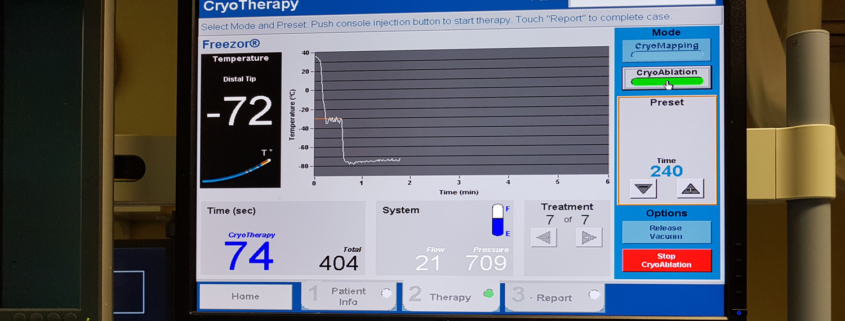

Krioablacija balonom je relativno nova metoda za ablaciju paroksizmalne fibrilacije atrija koja se razvila kao alternativa radiofrekventnoj ablaciji.